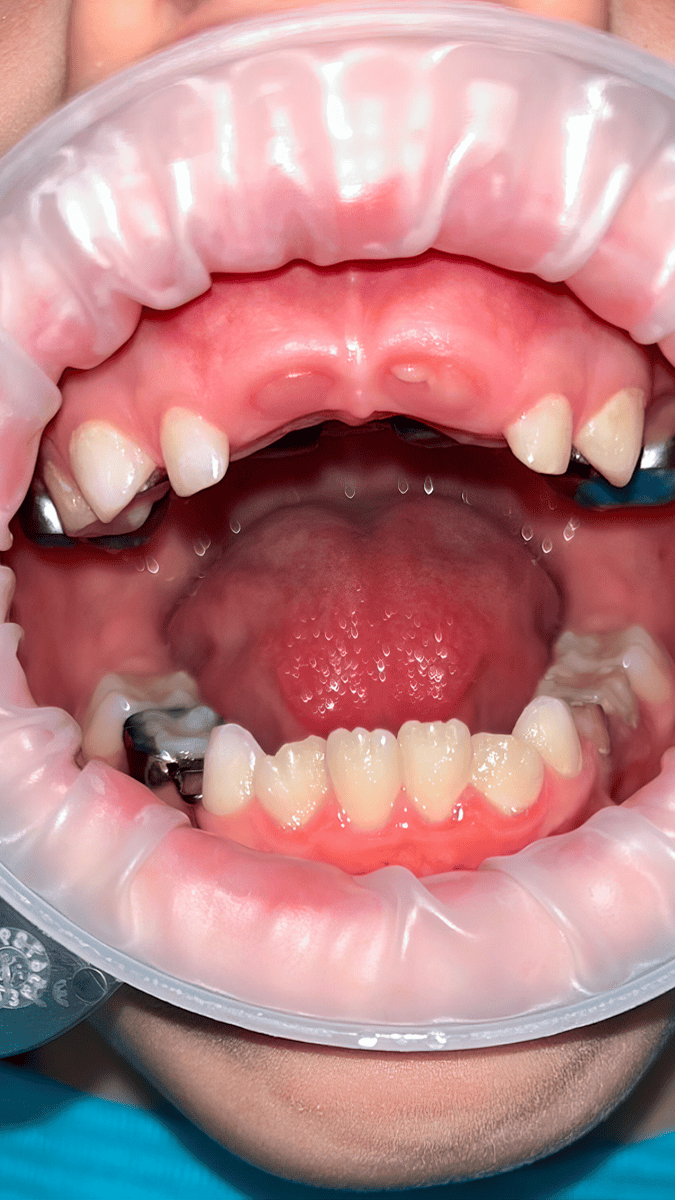

Фото «Альвеолит»: Шкурат Ольга Владимировна Кейс № 18